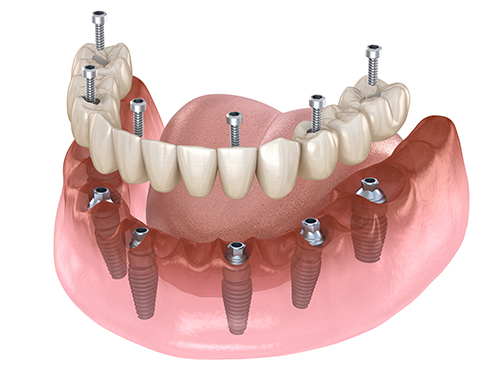

上あごの骨が非常に薄く、そのままではインプラントを埋め込むことができないため、Xマークを使用したザイゴマ(頬骨)インプラントおよびプテリゴイド(蝶形骨)インプラントを行ったケース。

ザイゴマインプラント

上あごの骨が十分にない場合には、強固な頬骨に長めのインプラントを埋め込むことで、しっかりとインプラントを固定することができます。

プテリゴイド(蝶形骨)インプラント

骨移植など、サイナスリフトを避けた手術を行えます。X-ガイドにより、正確な手術が可能です。